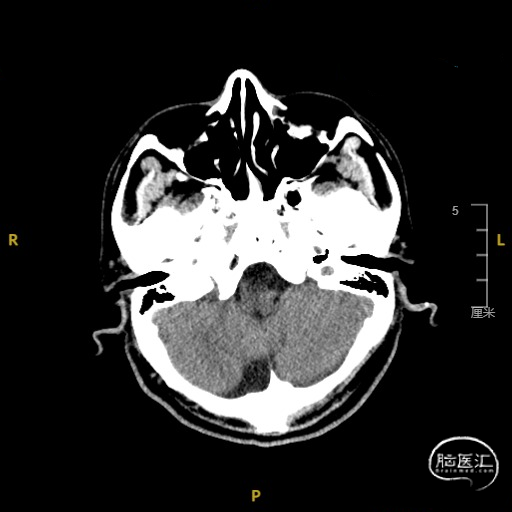

➢ 门诊头CT检查

现病史:患者于入院前3天无明显诱因出现言语不利,表现为社体笨拙,吐字不清晰,症状呈持续性,无头晕、视物旋转,无耳鸣、听力减退,无头痛、发热、恶心、呕吐,无视物不清、视物成双,无饮水呛咳、吞咽困难,无肢体活动障碍,无肢体抽搐、口吐白沫,无意识障碍及大小便失禁,就诊于我院门诊,查头CT示脑内散在缺血灶,完善颈部血管超声示双侧颈动脉内中膜增厚伴多发斑块形成,右侧颈内动脉狭窄(70-99%),右侧锁骨下动脉起始处斑块形成。TCD提示右侧大脑半球低搏动改变——考虑右侧颈内动脉颅外段病变,右侧颈内-外侧支开放,右侧大脑后动脉流速代偿性增快,左侧椎动脉狭窄(轻度)。为进一步诊治收住入院。